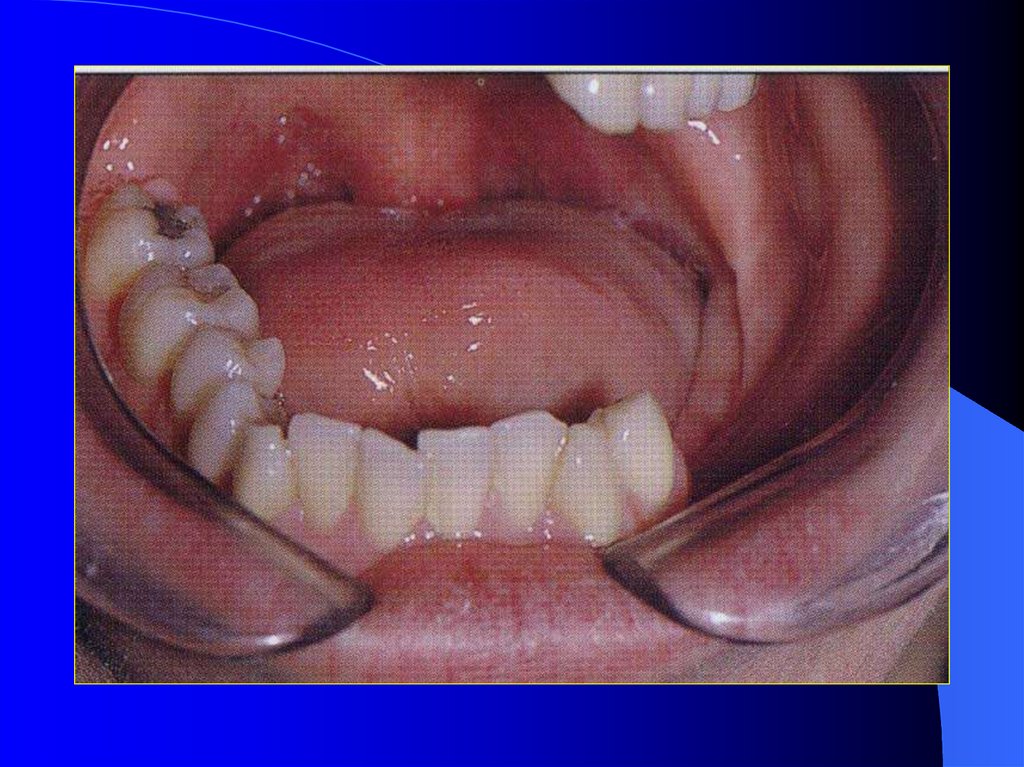

12. Altçene devamlılığı bozulmayan dişsiz hastalar

Dişler olmadığı için

protetik tedavi önceki

gruba göre daha

zordur. Çevre

dokuların kaybı,

lokalize parestezi,

değişmiş dil

hareketleri başarıyı

olumsuz etkiler.